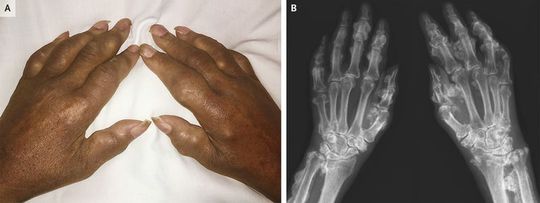

A 65-year-old woman who had undergone lung transplantation 8 years earlier was evaluated by the rheumatology service for progressive swelling in both hands and diffuse body pain. Since transplantation, the patient had received antifungal prophylaxis with daily voriconazole. On examination, there was prominent joint and soft-tissue swelling and pain in both hands (Panel A), restricted range of motion in both shoulders, and tenderness on palpation of the bony prominences of the shoulders, elbows, neck, lower back, and knees. The alkaline phosphatase level was 742 U per liter (reference range, 34 to 123). Radiographs of the hands (Panel B) showed dense, irregular, nodular periostitis of the bones in her hands and wrists, a finding consistent with voriconazole-induced periostitis. Voriconazole is a trifluorinated antifungal medication; the mechanism of the periostitis is thought to be related to the effects of fluoride on bone. Voriconazole was discontinued in the patient. After consultation with the transplantation team, no further antifungal prophylaxis was initiated. At a 7-month follow-up visit, the pain had decreased, although limitations in range of motion and bony swelling of the hands persisted.